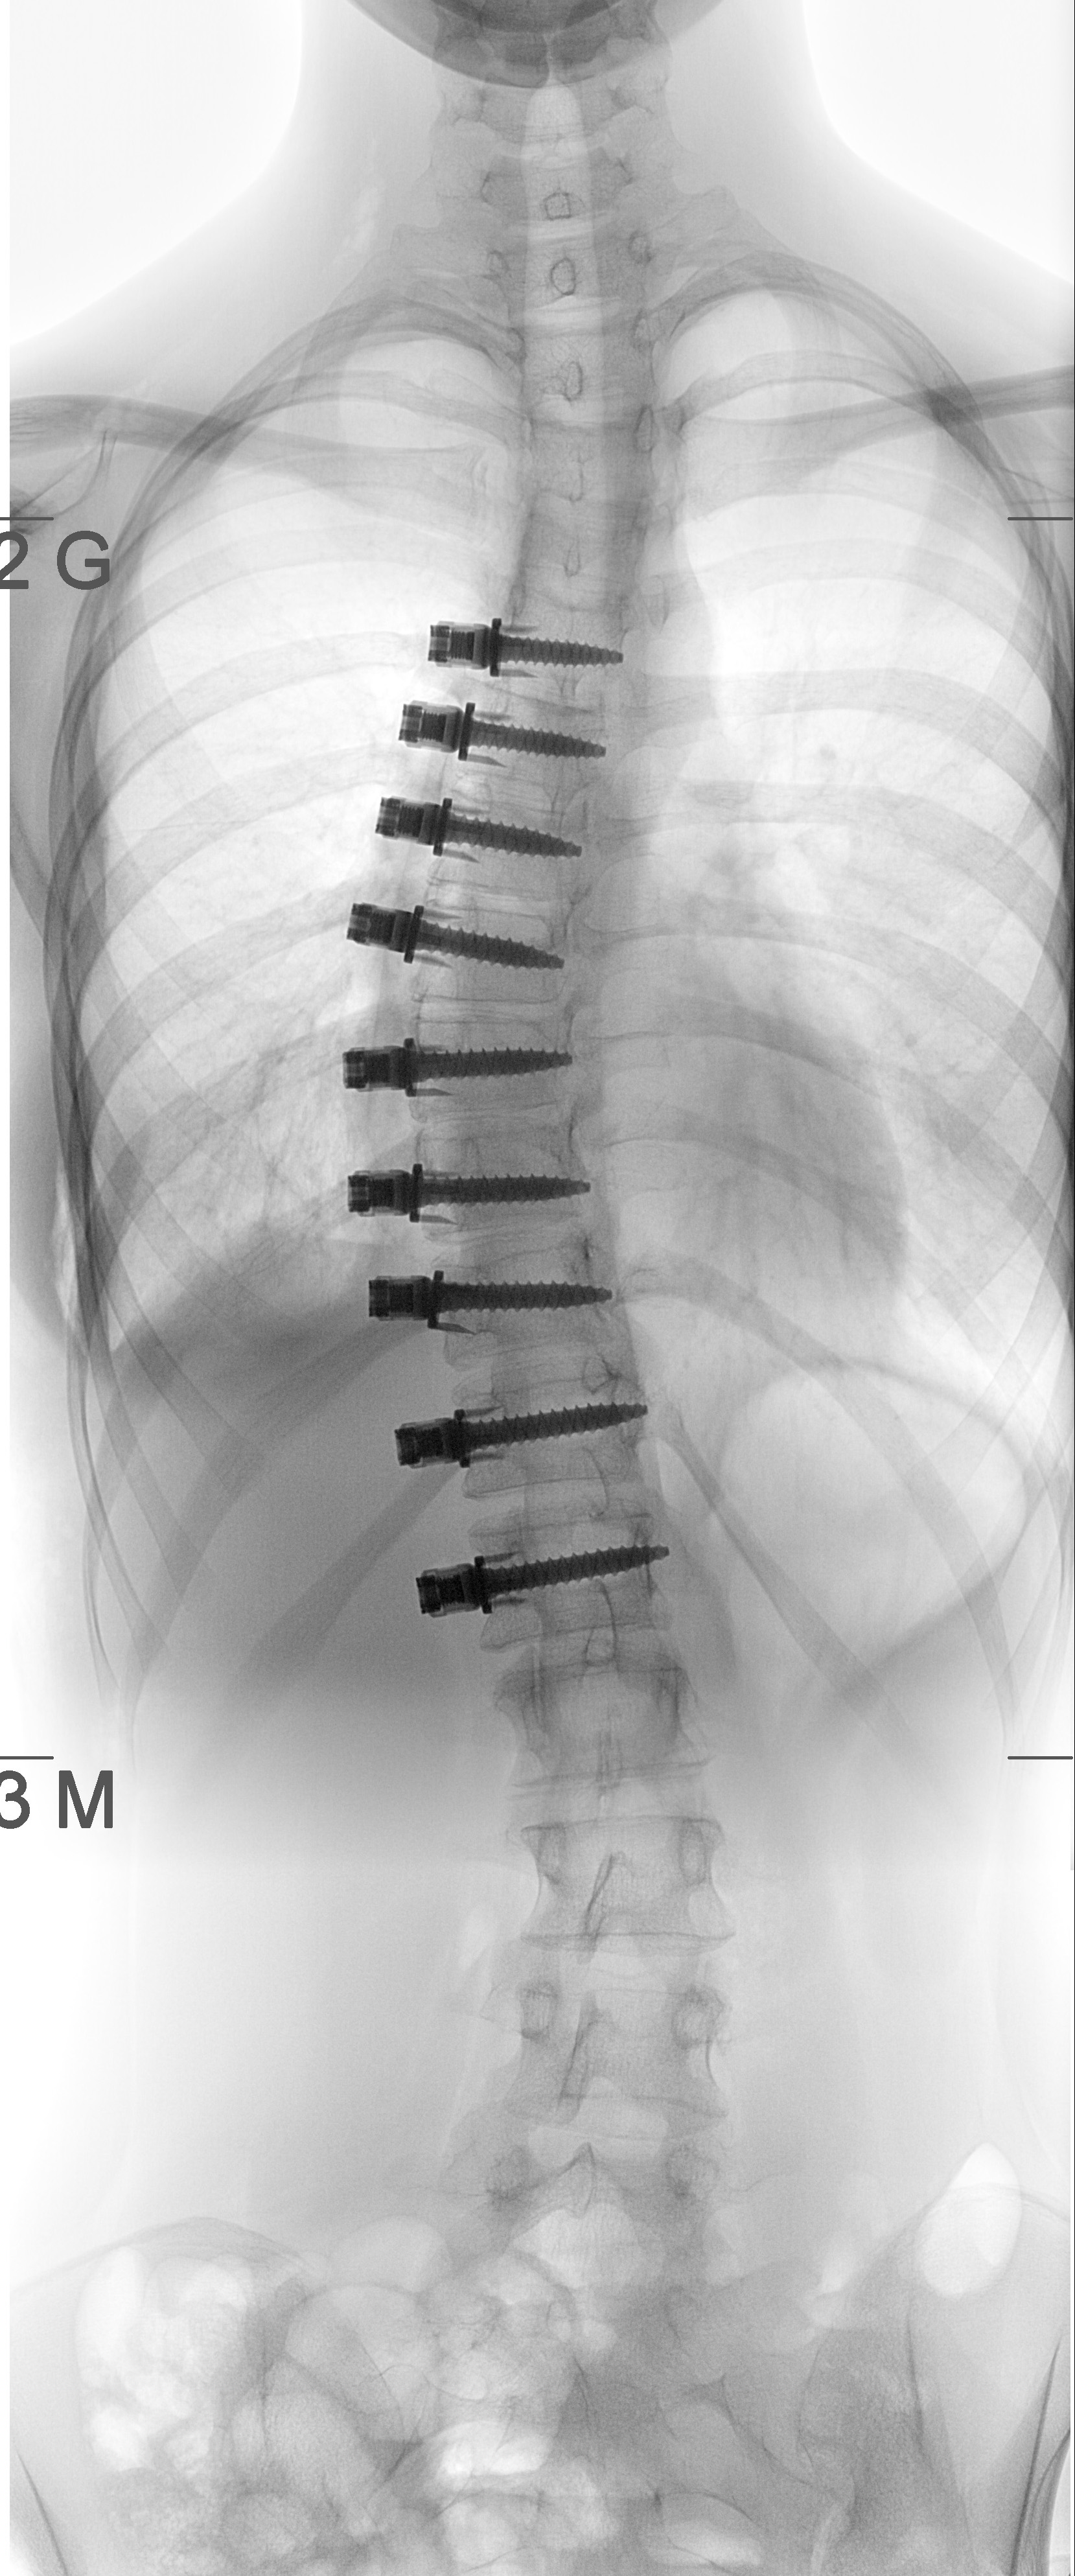

Am 29. August 2018 war es dann so weit: Die Experten der Klinischen Abteilung fĂŒr KinderorthopĂ€die der Univ.-Klinik fĂŒr Kinder- und Jugendchirurgie korrigierten Katrins AIS mithilfe des neuen Verfahrens. „Dabei werden spezielle Schrauben in die Wirbelkörper eingesetzt und mit einem Kunststoffseil auf der konvexen Seite der KrĂŒmmung verspannt – in der Fachsprache unter dem Begriff Vertebral Body Tethering, kurz VBT, bekannt“, fasst Ass.-Dr. Martin MĂŒnnich, der mit Saraph die OP durchgefĂŒhrt hat, die Vorgehensweise zusammen. Der Effekt: Dem verkrĂŒmmten Teil der WirbelsĂ€ule wird durch die Spannung auf der Außenseite entgegengewirkt, sodass er sich sukzessive aufrichtet ohne Beweglichkeit einzubĂŒĂŸen.